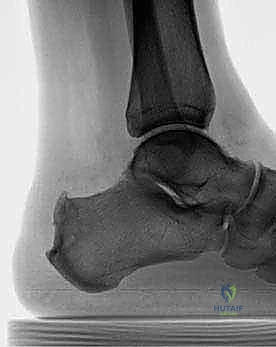

- الأشعة السينية (X-rays): ضرورية لرؤية تكلسات الوتر، وحجم النتوء العظمي (تشوه هاغلوند)، وزاوية عظم الكعب.

- تشوه هاغلوند (Haglund's Deformity): في كثير من المرضى، ينمو نتوء عظمي بارز في الجزء الخلفي العلوي من عظم الكعب. هذا النتوء يحتك باستمرار بالوتر والأكياس الزلالية مع كل خطوة.

- بروز عظمي مرئي: ظهور كتلة صلبة أو نتوء في مؤخرة الحذاء (تشوه هاغلوند).